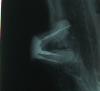

Lyu9mila Опубликовано 7 ноября, 2009 Автор Поделиться Опубликовано 7 ноября, 2009 (изменено) Новые снимки. Прицельный: №16, №17- до удаления 17. И гайморовы пазухи на сегодняшний день. К стоматологу хожу 2 раза в год, а картина получается такая, что словно я с луны свалилась или из пещеры вылезла. Может возраст? С весны, когда "полетел" мост, проблемы с ртом повисли на мне тяжким бременем. И всё сложно. и трудно решимо, и одномоментно ( терапия, хирургия, протезирование). И самое тяжкое - принятие решение за мной!!! А что я могу? С нумерацией зубов разбиралась неделю... Грустно. Всем спасибо. Изменено 7 ноября, 2009 пользователем Lyu9mila Ссылка на комментарий

SoulTreatment Опубликовано 8 ноября, 2009 Поделиться Опубликовано 8 ноября, 2009 Сделайте прицел нижней правой восьмерки... во время обострения при накусывании боль в области уха усиливается? Ссылка на комментарий

Lyu9mila Опубликовано 8 ноября, 2009 Автор Поделиться Опубликовано 8 ноября, 2009 Да, порой очень болезненно именно при надкусывании. Это что, ещё один проблемный зуб №38? Ссылка на комментарий

SoulTreatment Опубликовано 8 ноября, 2009 Поделиться Опубликовано 8 ноября, 2009 да... мое мнение, что именно от него у Вас проблемы болевого характера! но заниматься надо практически всеми зубами, увы, без исключения! Ссылка на комментарий

Lyu9mila Опубликовано 9 ноября, 2009 Автор Поделиться Опубликовано 9 ноября, 2009 Ваш вердикт для №46? Его пытались сохранить, залечивали, но... Ссылка на комментарий

доминика Опубликовано 9 ноября, 2009 Поделиться Опубликовано 9 ноября, 2009 Ваш вердикт для №46? Его пытались сохранить, залечивали, но... ненадежный ,и это 36 Ссылка на комментарий

Андрей Опубликовано 9 ноября, 2009 Поделиться Опубликовано 9 ноября, 2009 Ваш вердикт для №46? Его пытались сохранить, залечивали, но... Зуб не стоит вложения денег. Ссылка на комментарий

Lyu9mila Опубликовано 11 ноября, 2009 Автор Поделиться Опубликовано 11 ноября, 2009 Н/Ч слева. Благодарю всех докторов за консультацию. Можно ещё один вопрос? На панорамном снимке, в десне на месте удалённого №44 что - то белое - это не кусочек корня зуба? Спасибо. Ссылка на комментарий

x3m Опубликовано 11 ноября, 2009 Поделиться Опубликовано 11 ноября, 2009 это область 34 (не 44), т.е. слева у Вас.имхо, выведенный за корень пломбировочный материал.зуб убрали, а материал остался. Ссылка на комментарий

доминика Опубликовано 11 ноября, 2009 Поделиться Опубликовано 11 ноября, 2009 а материал остался.+1 Ссылка на комментарий